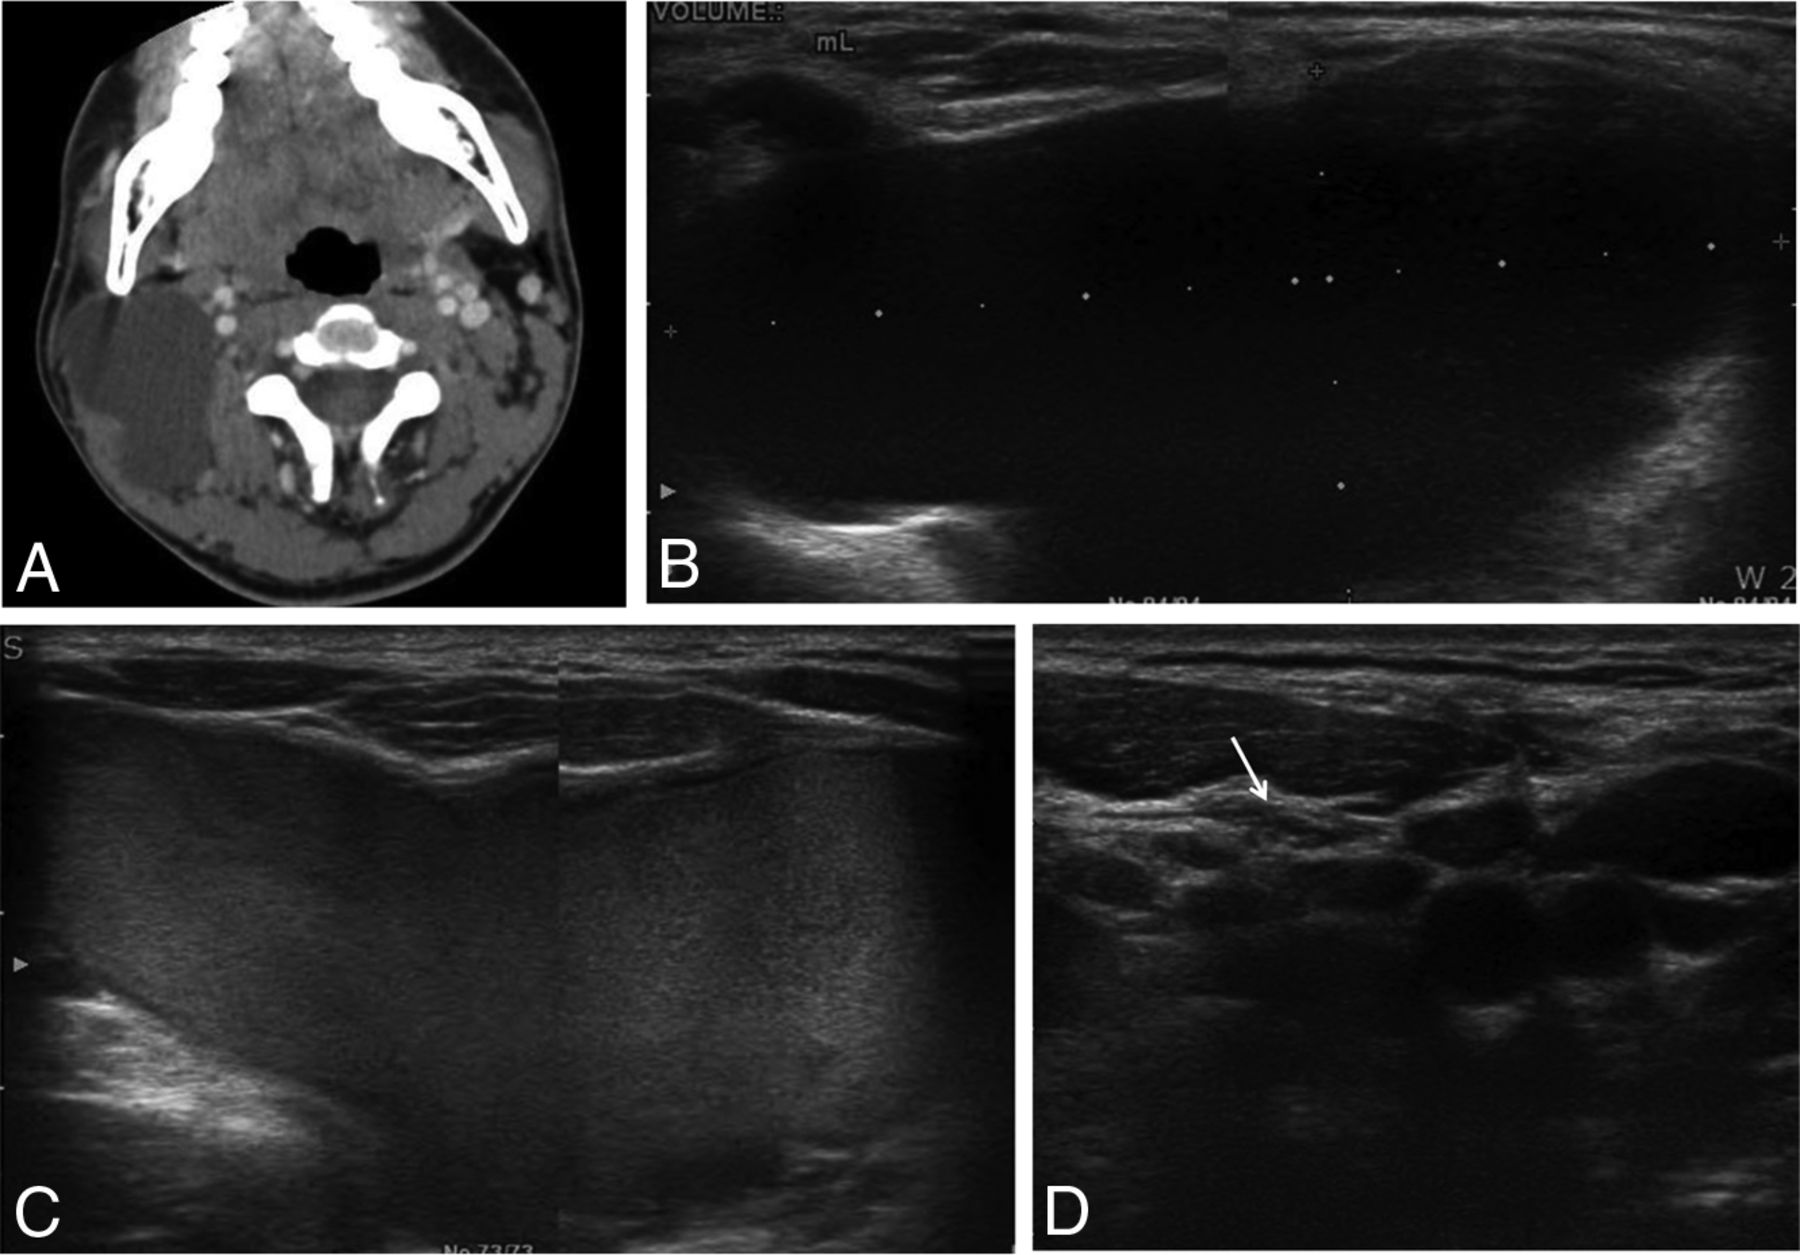

A 15-year-old adolescent boy with a right-neck mass. A and B, Transverse US and CT scans show a 7-cm cystic mass in the right neck (volume, 36.6 mL). C, During the ethanol ablation, intracystic hemorrhage developed after aspiration of internal contents. D, However, after a second session of ethanol ablation, the cystic mass had disappeared on follow-up US (arrow).